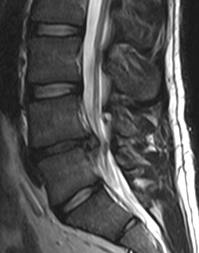

Кости, образующие позвоночник, отделены друг от друга амортизирующие маленькими дисками. По форме спинальные диски круглые и плоские, с плотным наружным слоем (капсула или кольцо), окружающее студнеообразное вещество (ядро). Когда эти диски здоровы, они действуют как амортизаторы сотрясений позвоночника и придают позвоночнику гибкость. При повреждении дисков в результате травмы, естественного износа и старения либо заболевания они могут аномально выпячиваться или разрываться (так называемая грыжа). Аномально выпячивающийся или разорвавшийся диск называют грыжей диска, или иногда протрузией диска.

Протрузия или грыжа диска может сдавливать нерв в том месте, где у Вас сзади от спинного мозга отходят нервные веточки. Такое сдавление может вызывать боль, онемение, покалывание, слабость или утрату рефлексов в ноге. Она может вызывать боль в пояснице, а может и нет. Однако во многих случаях грыжа диска не вызывает никаких симптомов. Если МРТ-исследование показало у Вас наличие грыжи диска, Ваш доктор тщательно сопоставит результаты МРТ с результатами Вашего медицинского осмотра для того, чтобы убедиться в том, что визуализируемая на МРТ грыжа диска является наиболее вероятной причиной Ваших симптомов.

- Такие диагностические методы исследования, как магнитно-резонансная томография (МРТ), компьютерная томография указывают на то, что Ваша грыжа диска может быть излечена хирургически.